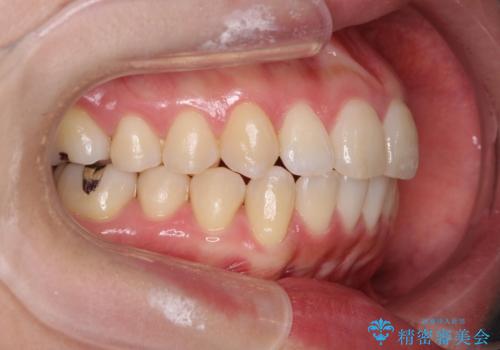

上下の歯は、上顎の歯が相対的に前に位置する咬合関係で押し出されるように前歯に角度がついている状態です。

咬合関係の改善、前歯の角度、がたつきを改善するため、マイクロインプラントを用いて上顎の奥歯を後方へ移動させていきます。

矯正治療後、前歯のがたつき、咬合関係が改善され満足いただくことができました。